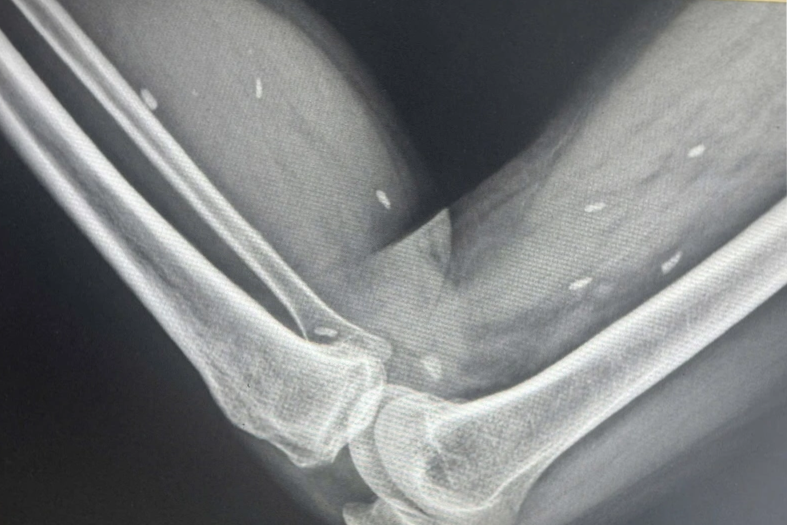

Hình ảnh X-quang gây sốc ở người đàn ông có thói quen ăn đồ sống

Đến bệnh viện trong tình trạng đau nhức, mệt mỏi kéo dài, người đàn ông bất ngờ khi nhìn thấy phim X-quang hiện hình ảnh nhiều kén sán do thói quen ăn đồ sống.